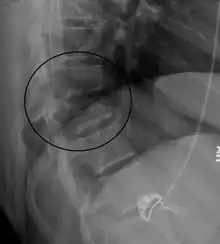

| A Chance fracture of T10 and fracture of T9 due to a lapbelt during an MVC. | |